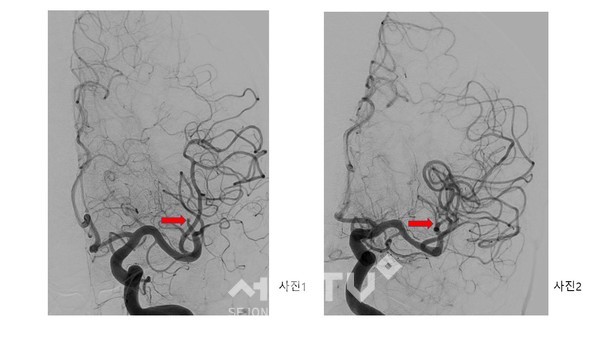

이번 시술을 집도한 신경외과 변형수 교수는 응급 뇌혈관 조영술을 통해 환자 상태를 살펴본 결과, 왼쪽 뇌의 50%에 혈액을 공급하는 중요한 혈관이 막힌 것을 확인하고 흡입 혈전제거술을 통해 1시간 이내에 재개통술을 성공적으로 마쳤다고 설명했다.

뇌혈관 재개통술은 갑자기 뇌혈관이 막혀 발생한 뇌경색 환자가 골든 타임 이내에 내원했을 때 막힌 혈관을 뚫어주는 치료로 뇌 손상을 최소화할 수 있는 최선의 치료법이다.